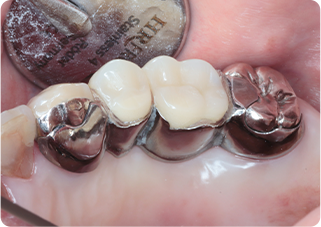

インプラント&セラミッククラウン&オーバーレイ症例

術前

術後

| 主訴 | 右下のブリッジに物が挟まる |

|---|---|

| 治療期間/回数 | 4ヵ月、10回 |

| 価格(税込) | 836,000円 |

| リスク・副作用 | 神経・血管損傷、術後感染、出血、インプラント周囲炎、上部構造破損、セラミックの破損・脱離の可能性 |

| ポイント | ブリッジの支台歯はセラミックに置き換え、ダミーの歯のところにインプラントを埋入した。セラミックはなるべく周りの歯と色を合わせて作製している。 |